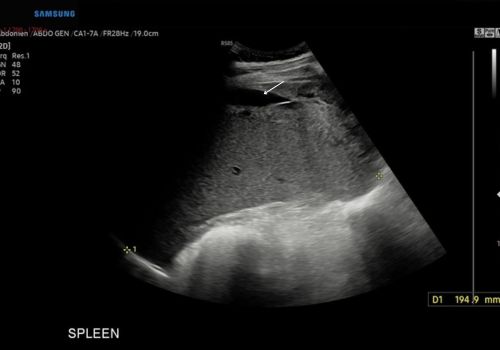

B Mode ultrasound findings confirmed hepatosplenomegaly along with a small volume of free fluid.

Figure 1 above Ultrasound confirms splenomegaly with a small volume of free fluid(arrow).